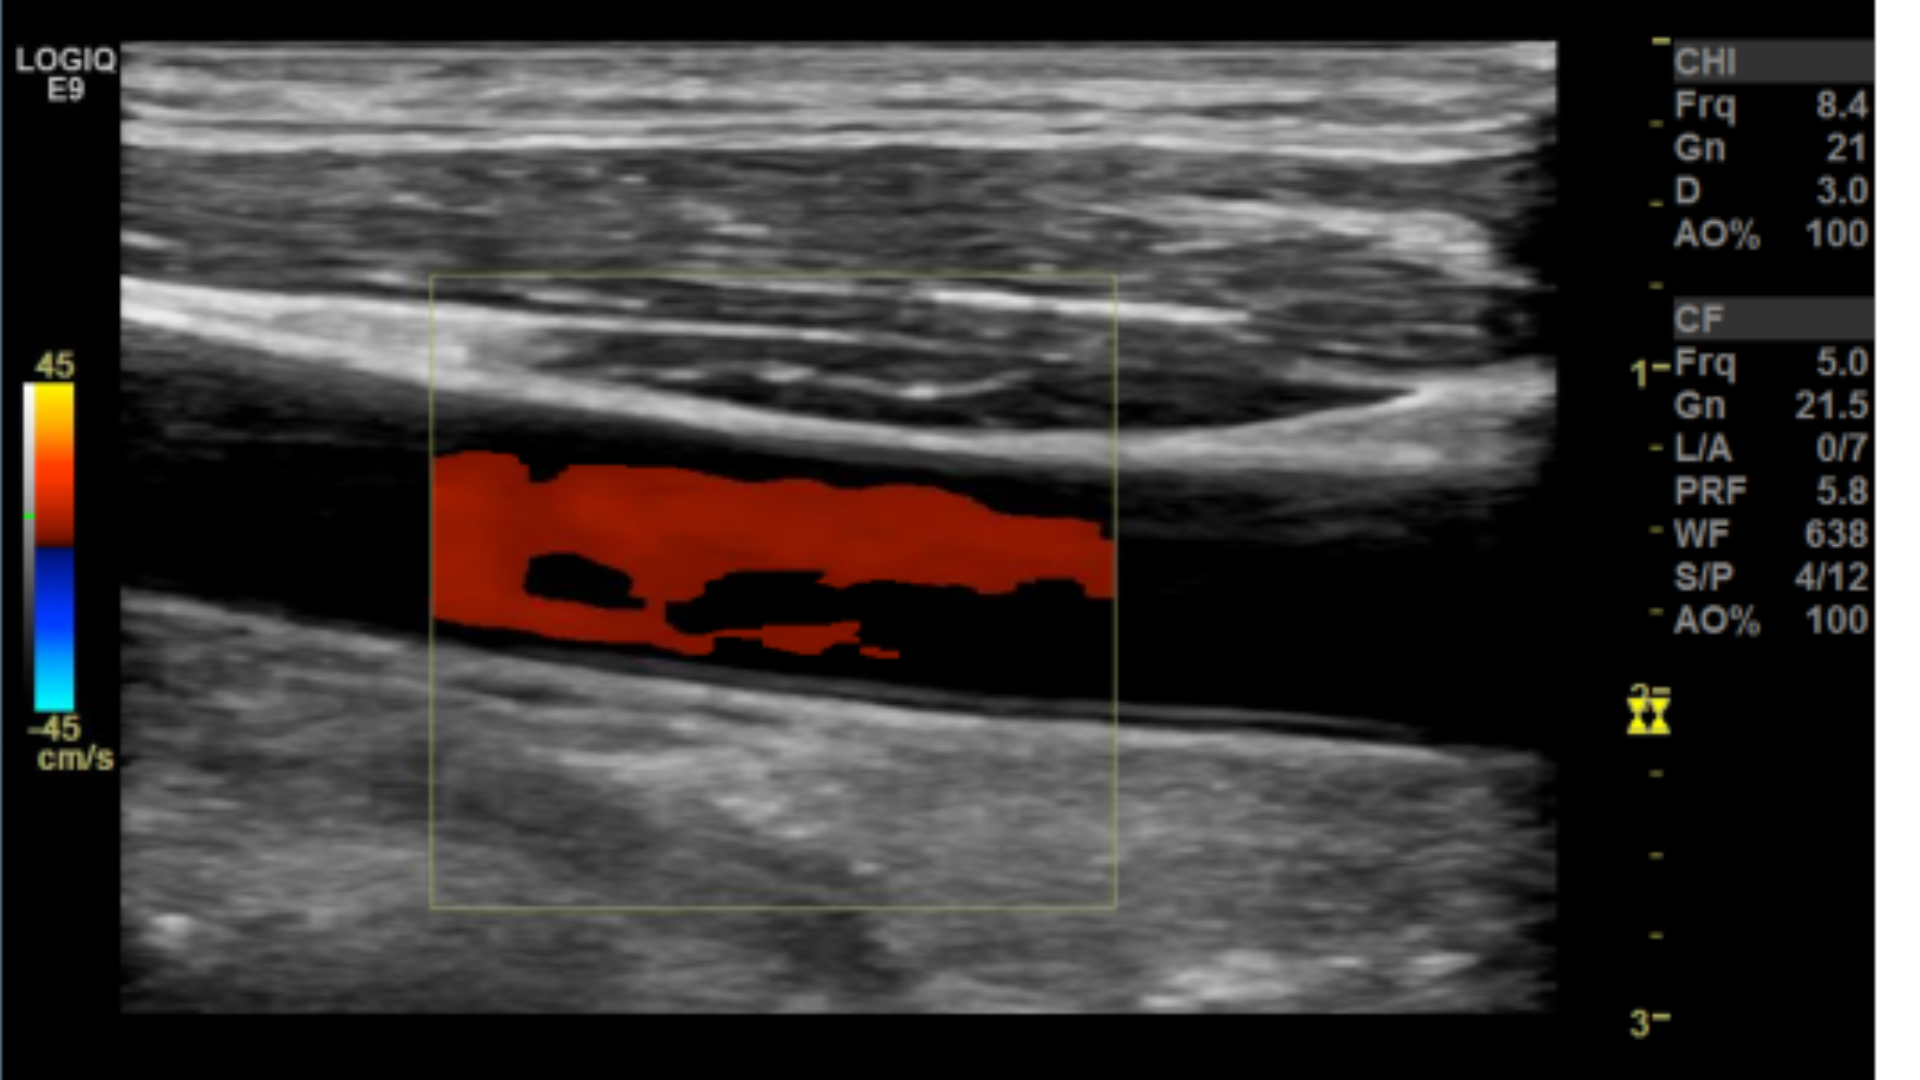

Taking technically superior images not only looks aesthetically pleasing, it is important in that it provides accurate data to render a correct diagnosis. A few parameters you may want to tweak are the doppler scale or pulse repetition frequency PRF and gain for both color and spectral doppler.

Too low of a scale and you’ll get aliasing which makes getting a proper velocity impossible.

Scale/PRF too low

Many people have trouble on how to set the color box. A quick way to get it right is to make sure the steered ultrasound beam and vessel meet an acute angle 60° or less.

Correct Color box angle

Sub-optimal angle

Incorrect angle